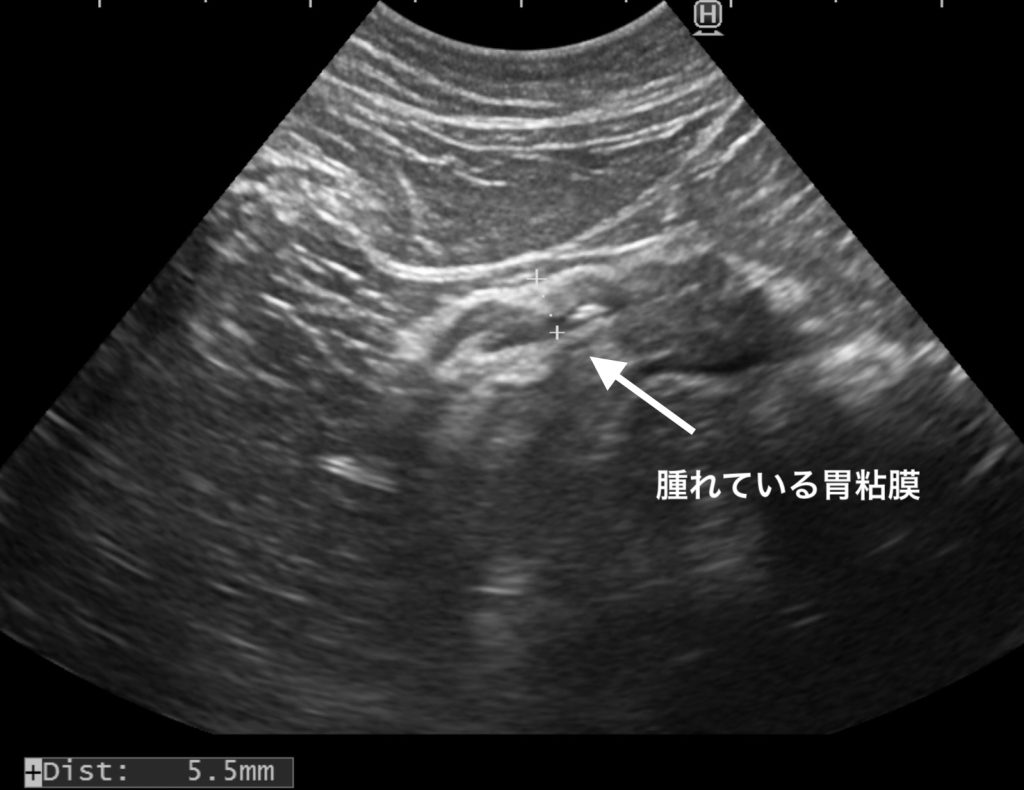

嘔吐がある場合には、胃粘膜が腫れていることが多いです。

胃粘膜の腫れ方は、さまざまなパターンがありますが、

今回ご紹介した子は、内視鏡検査にて『リンパ腫』の診断がでています。

*ダイナミックな変化ではなくても、悪性腫瘍のことがございますので、注意が必要です。